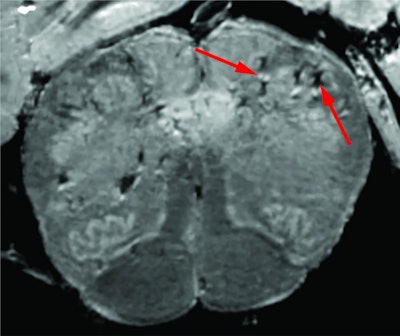

The MRI scans revealed hyperintensities and hypointensities, which the investigators then examined more closely under a microscope. The hyperintensities had blood vessels thinner than normal and that sometimes leaked proteins into the brain, which triggered an immune reaction. The hypointensities included clotted and leaky blood vessels but no immune response.

High-resolution MRI scan of a patient's brain stem. Arrows point to light and dark spots that are indicative of blood vessel damage observed in the study. Image courtesy of the NIH.Nath and colleagues found no signs of SARS-CoV-2 infection in the tissue samples.

"Originally, we expected to see damage that is caused by a lack of oxygen. Instead, we saw multifocal areas of damage that [are] usually associated with strokes and neuroinflammatory diseases," Nath said in the NIH statement. "In the future, we plan to study how COVID-19 harms the brain's blood vessels and whether that produces some of the short- and long-term symptoms we see in patients."